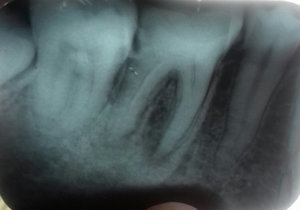

Здравствуйте. От 6-го нижнего зуба остался один корень. Зуб не болит, нервы удалены, каналы запломбированы. Зуб нужно удалить. Насколько сложна данная процедура и будут ли мне резать десну? Спасибо.

Добрый день! Если разрушение зуба не ниже основания десны и при этом каналы хорошо (!!!) пролечены (нет воспалительных процессов, грануляций), и ткани зуба плотные, то зуб можно восстановить культевой восстановительной вкладкой, а затем коронкой. Я вам рекомендую обратиться на прием к грамотному ортопеду для анализа состояния корня зуба. Если потребуется моя помощь , обращайтесь всегда рад вам помочь.